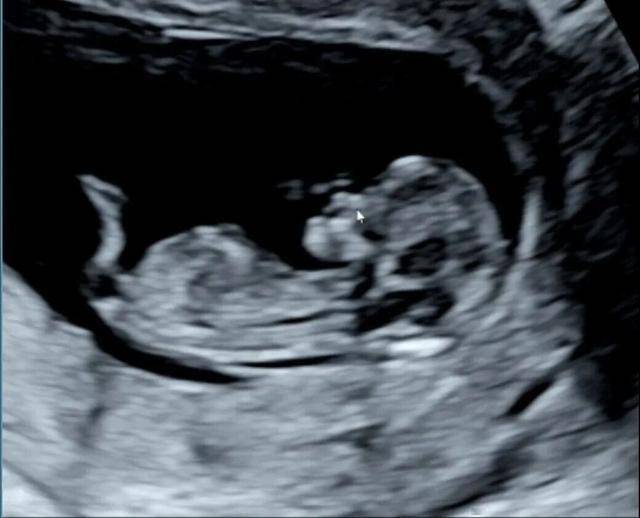

9月,因为孕吐太严重,瘦了20多斤,脸上胸前起满了红疹,辗转三家医院,扎了不知道多少针,每天要在医院输液从早到晚,终于在护士给我换留置针重新扎针的时候,嚎啕大哭,太委屈了太委屈了,也好辛苦。第二天做检查听到肚子里小孩咚咚有力的心跳时,躺在检查台上再次落泪,那一刻,我暗暗发誓,不管我的小孩是男是女,以后想结婚就结婚,不想结婚就不结,我的女儿或者是儿媳妇想养小孩就养,不想养,我也坚定支持。正是体会到了生命的不易,我更加坚定了我的小孩以后只需要健康幸福的想法。大概是要在医院度过中秋国庆,希望度过这次难关后一切顺利。